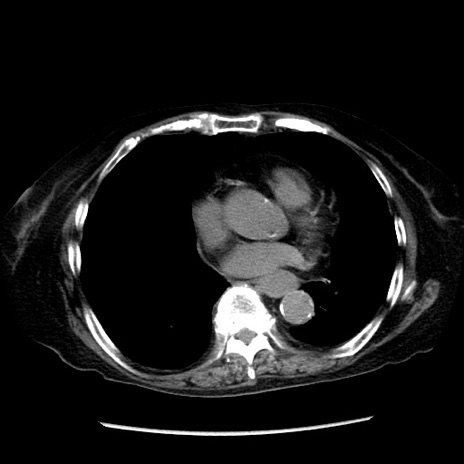

症例14(横断像)

【症例】 90歳代女性

【主訴】 腹痛・嘔吐

【現病歴】今朝から左側腹部痛を認めた。 経過観察していたが、嘔吐を認めたため来院。

【既往歴】 子宮癌術後

【身体所見】 意識清明、BP 127/54mmHg、P 98bpm Sp02 95%(RA)、BT 35.8°C、腹部平坦・軟腸ぜん動音聴取良好、右下腹部圧痛(+) 反跳痛なし

【データ】WBC 9800、CRP 0.46